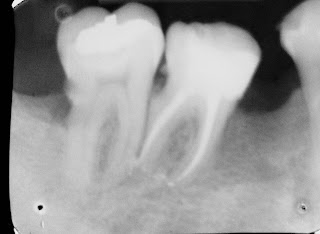

Caso Clínico Interessante do Prof. Carlos E. da Silveira Bueno - Tratamento Endodôntico com Sistema Reciprocante / PathFiles / 4o Canal

O caso a seguir nos mostra a importância do conhecimento da anatomia de molares superiores.

O tratamento Endodôntico do dente 17 foi realizado em uma única sessão com

auxílio de instrumento Reciprocante Wave One e Pathfiles. Porém ao final da obturação

dos canais Vestibulares (MV e DV) e Palatino observou-se um ponto mais próximo ao canal Palatino (incomum nesses casos) que denotou ser o 4o canal deste elemento. Dessa forma sua instrumentação e obturação foi realizada em sequência.

Utilização de Limas PathFiles

Instrumentação Reciprocante - WaveOne

Irrigação com Sol. de Hipoclorito de Sódio 2,5% e ao final EDTA 17%

Ambas ativadas com PUI - Passive Ultrasonic Irrigation

PUI - (3 ciclos de 10s por canal/por solução - Hipoclorito/EDTA/Hipoclorito)

Obturação com Onda Contínua de Condensação + Cimento Ah-Plus

Selamento coronário pós-endodontia realizado com Cimpat e Resina Composta.